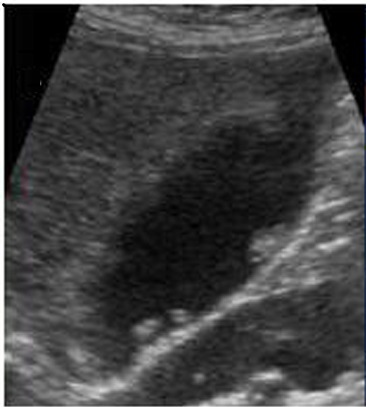

Aspect echographique d'une

adenomyomatose forme diffuse avec image

d'epaissisement globale de paroi de la vesicule

biliaire . Des nodules cholesterolique hyperechogene

intramural avec " comet sign " peut en se voyait

|